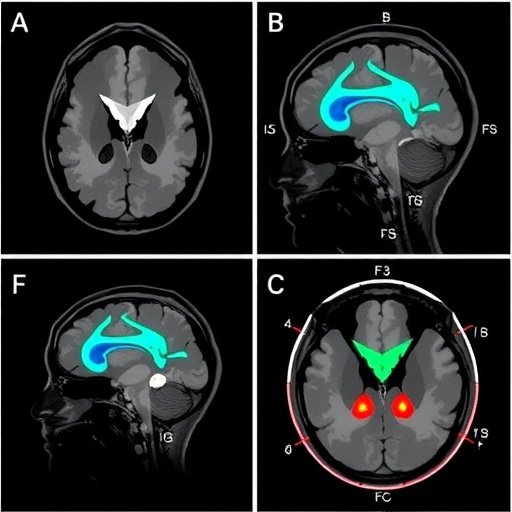

The innovative approach investigated by Zhuang and colleagues involves using multi-pool CEST MRI to provide a multifaceted view into the biochemical environment of brain tissues. This technique exploits the chemical exchange between protons in tissue and water protons, which can illuminate different molecular pools that may change in concentration during hypoxia. By leveraging this advanced imaging modality, clinicians could potentially discern the subtle biochemical shifts that are indicative of early pathological changes in the brain of affected neonates.

One of the standout features of multi-pool CEST MRI is its capability to differentiate between various types of biochemical exchanges. Unlike traditional imaging modalities that provide limited information, CEST MRI delivers insights into the molecular microenvironment, including variations in metabolites that are crucial to the pathophysiology of brain lesions. The ability to visualize these changes at a molecular level allows for an unprecedented understanding of the dynamics of HIE and could lead to the development of more targeted therapeutic strategies.

In their study, Zhuang and colleagues conducted a series of experiments that involved measuring the CEST signals from various neuron-related metabolites in animal models mimicking HIE. The results indicated that specific alterations in the concentration of these metabolites could be linked to different grades of hypoxic-ischemic injury. By correlating CEST imaging findings with histopathological assessments, the team was able to establish a robust framework for interpreting the biochemical alterations seen during HIE, thus validating the use of CEST MRI as a promising diagnostic biomarker.